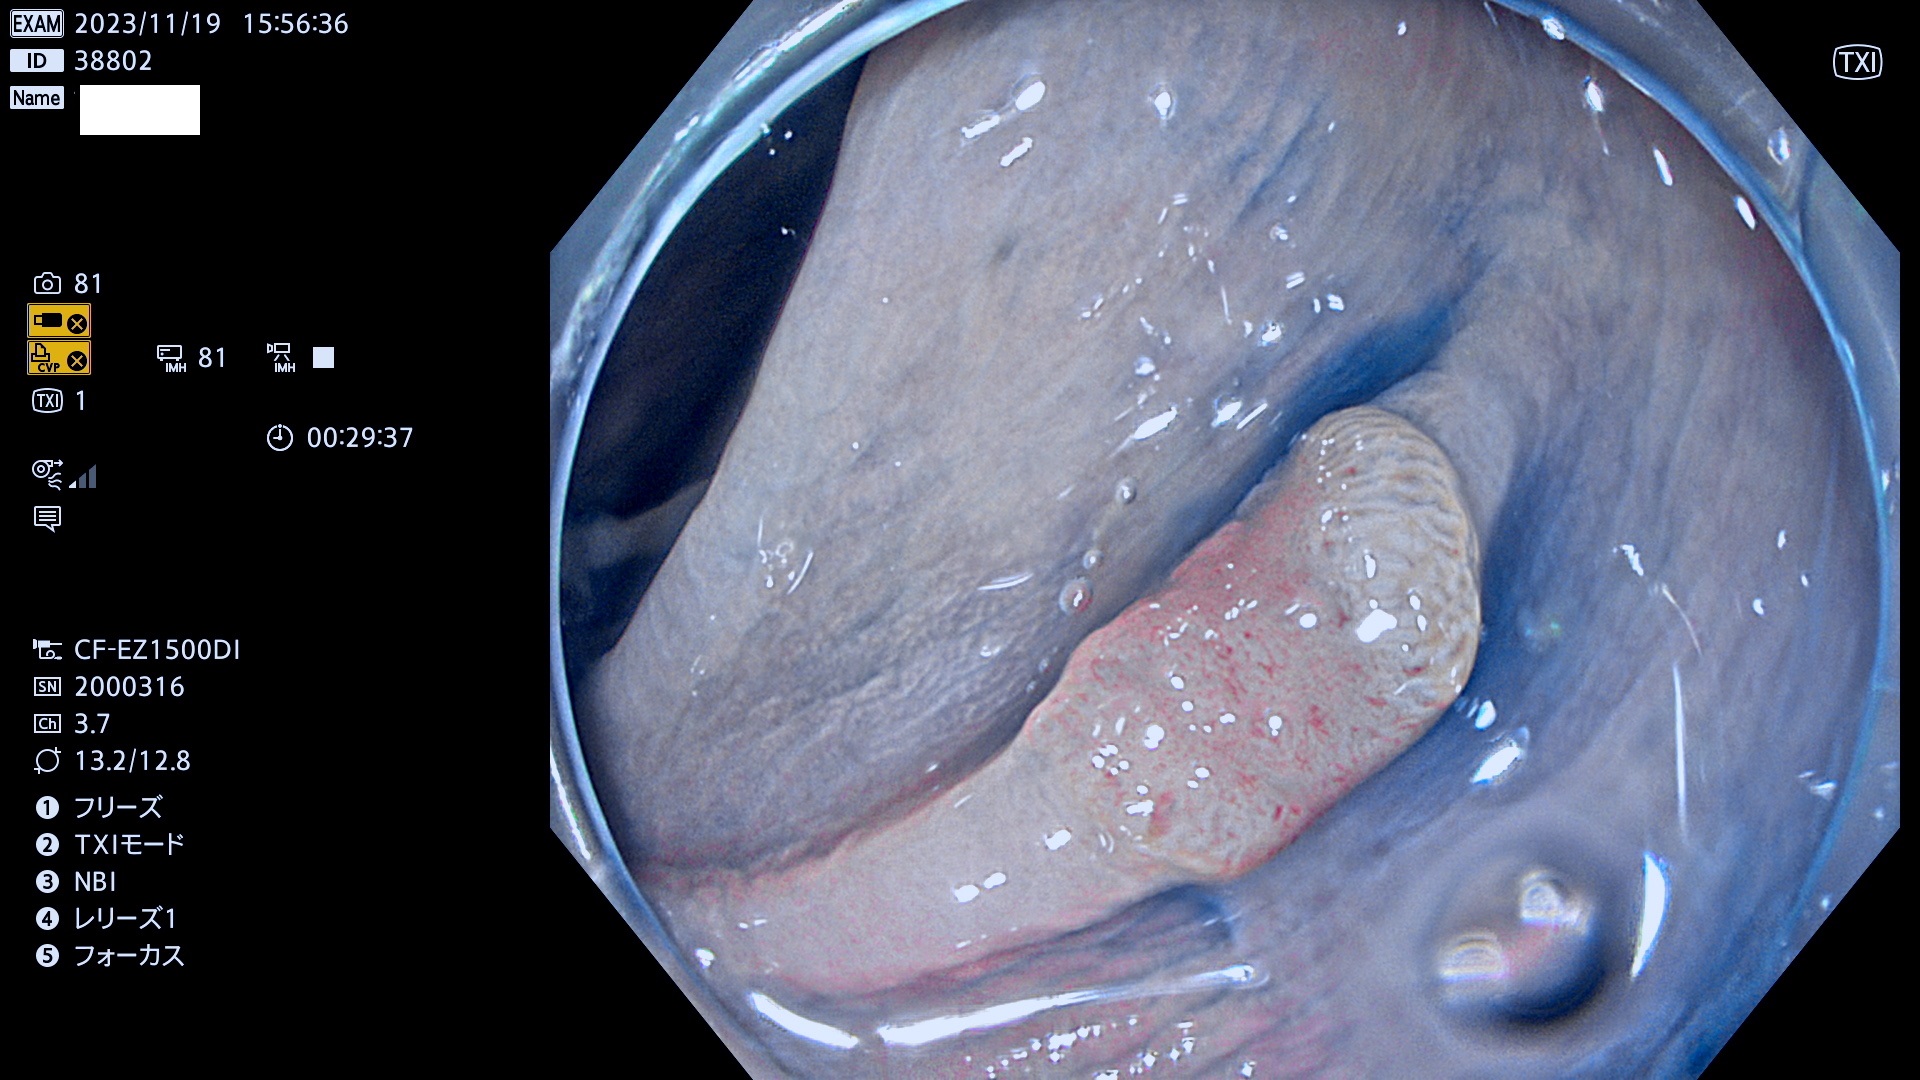

今週のUb、Uc型腺腫

表面型腺腫(Flat Adenoma)の中で、完全に平坦な物をUb、陥凹している物をUcと呼びます。平坦隆起型(Ua)よりも、発見が難しく危険な病変です。このタイプは「内視鏡後・大腸癌の重要犯人」であり、この発見率は「腺腫発見率」よりも、重要な意味があります。

毎週の検査(木・金・土・日)に発見されたUb、Uc型・腺腫を、その週の日曜の夜にUPし1週間、提示します。

抽出の対象期間 2023年11月16日(木)〜11月20(日)の5日間(60件の検査)11件